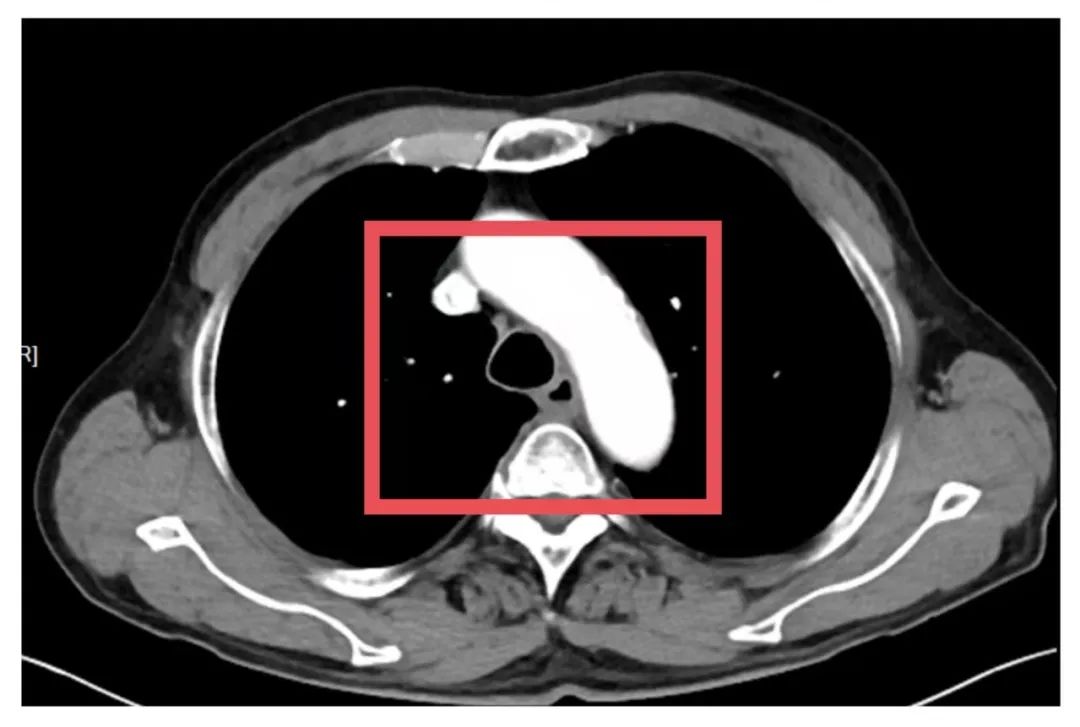

为了争取更大的根治机会,胸外科朱震主任医师为苏先生量身定制定了一套治疗方案——“免疫联合化疗”的新辅助治疗方案,先“软化”肿瘤、减少侵犯,再择期手术。治疗期间,苏先生接受了PD-1单抗与铂类+紫杉醇联合化疗。随着治疗推进,患者主诉症状显著缓解。2025年7月复查CT提示病灶缩小、边界清晰、与周围结构粘连减少,手术时机成熟。

术后,苏先生康复进展顺利,未出现肺部感染、吻合口瘘等并发症。最令人振奋的是,术后病理结果提示:肿瘤区域未见残留癌细胞,达到“病理完全缓解(pCR)”标准!这意味着,新辅助治疗获得高度成功,同时也为患者带来更佳的长期预后!

▲患者术前、术后影像对比